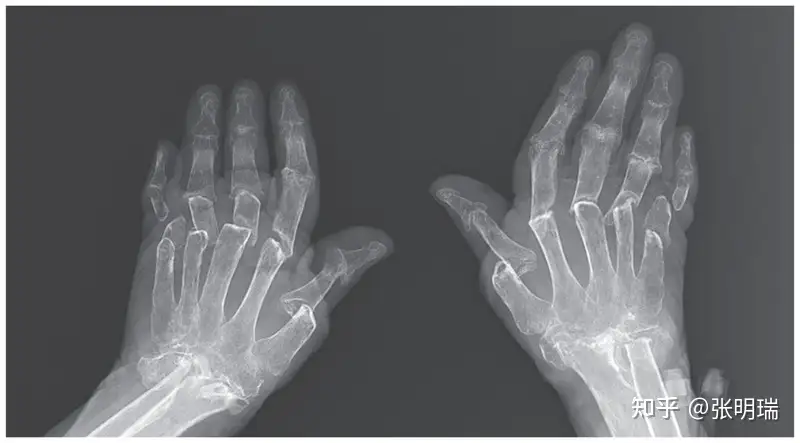

(手指关节炎的X光图片[2],这种情况下拿起手机都很困难,更别说点屏幕了 )

(手指关节炎的X光图片[2],这种情况下拿起手机都很困难,更别说点屏幕了 )